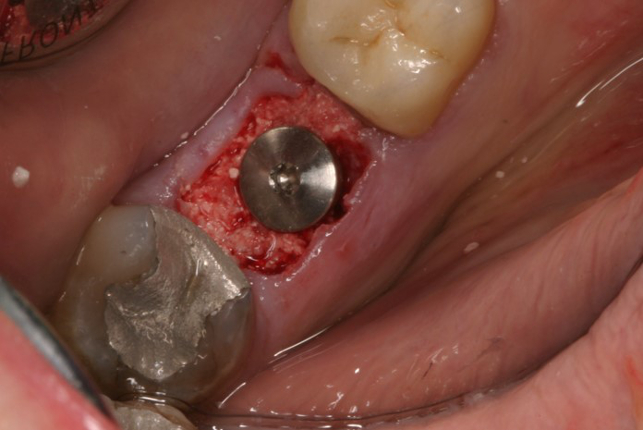

Fotos dos casos clínicos